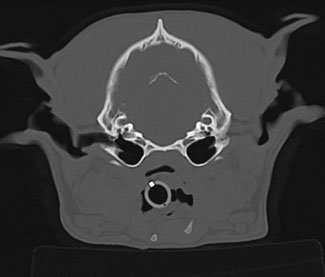

CT and MRI Scans

CT scanning, also known as “cat-scanning,” is a special type of x-ray exam in which a series of x-ray images, or “slices,” of your pet are obtained. CT scans are most useful when evaluating very complex parts of the body such as the head, chest, and some joints.